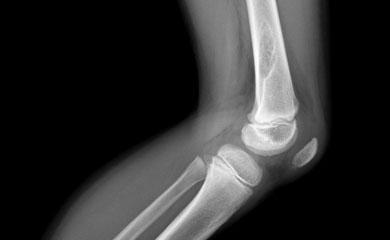

28 ?????? 2017/ ????? ????? ??????? ???????/????? ?????? ????? ??????? ?????? ?????????? ????? ?? ????? ?? ????? ????? ?????? ??? ?????? ????? ??? ???? 84 ????? ??????? ???? ?????? ??? ??????? ?? ???? ?????????. ??? ????? ????? ??? ???????? ???? ????? ?? ?????? ?? ?????? ??????? ?????? ?????? ??? ????????. ??? ??????? ?? ???? ?? ???????? ??? 4 ??? 6 ???? ?? ???????? ??????? ?? ???? ?????? ???????? ??? ????? ??????? ??????.